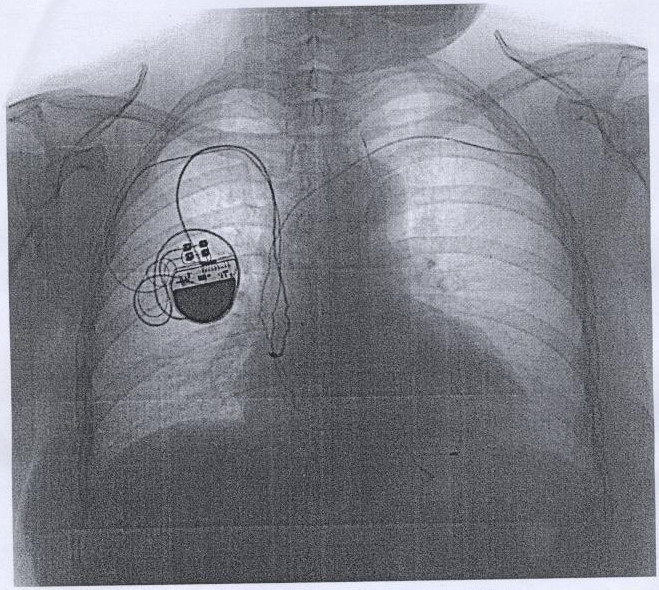

Был VVI, поставили DDD. Электрод остался.

Обсуждали здесь viewtopic.php?f=24&t=2655